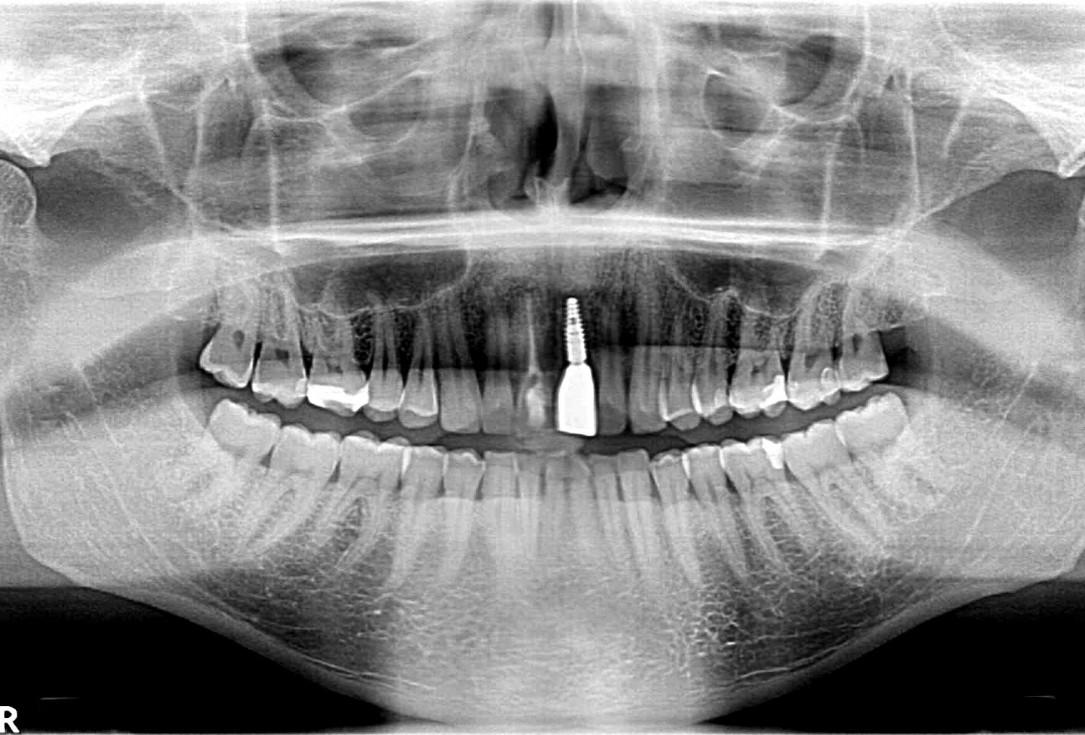

16/18 - Final X-ray